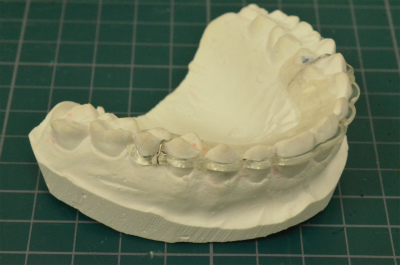

マウスピースタイプのクリアリテーナー

④ マウスピースタイプのリテーナーの見た目はいいけど汚れて色がくすみやすい・・

⑤ マウスピースタイプのリテーナーは装着感はいいけど、穴が開いたり破折しやすい・・

⑥ マウスピースタイプのリテーナーは歯の全体を覆ってしまうので上下顎のかみ合わせが変わってしまうことも・・

当院ではかつてはプレートタイプのリテーナーを選んでいたのですが、長期間にわたる保定具合(特に下顎の前歯)に難があることから上顎には主にマウスピースタイプのクリアリテーナー、下顎には主に固定式リテーナーを採用しております。

しかしクリアリテーナーは咬み合わせ具合などで比較的短期間に破折してしまうことも多々あり、再作を余儀なくされてしまいます。また審美リテーナーは、機能面では通常のプレート(床)タイプとほぼ同じです。

今回作り上げたリテーナーは見た目にも非常に優れており、プレートタイプとクリアリテーナーのいいとこどりをしたともいえます。

① 見た目に優れている

② 歯列保定の精度が良い

③ 壊れにくい構造

④ ろう着部分がないので銀ろうで黒ずんだりしない

⑤ 目に見える箇所の変色はほとんどなし

⑥ 装着感が良好

⑦ 大きさがコンパクトで装着時の違和感が少ない

など、これまで使用してきた各リテーナーのメリットはそのままでデメリットを極力排除した会心の出来でもあります。

画像のタイプは一例で、他にもバリエーションがあります。弾性を持つ透明の樹脂ワイヤーは見た目と機能だけではなく生体適合性にも非常に優れた医用高分子材料を使用しております。

他のリテーナーにはない一番の特徴は 表側・裏側ともに弾性機能を持つ樹脂ワイヤーで覆うことで歯の後戻りに対する動きを抑えていること です。